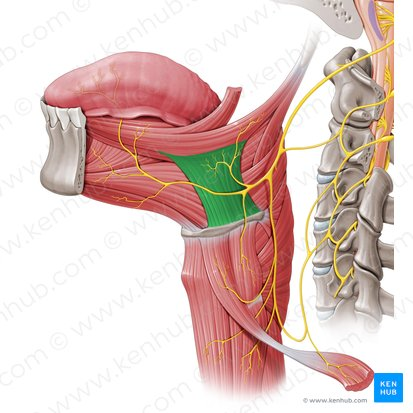

green highlight

Oropharynx

green highlight